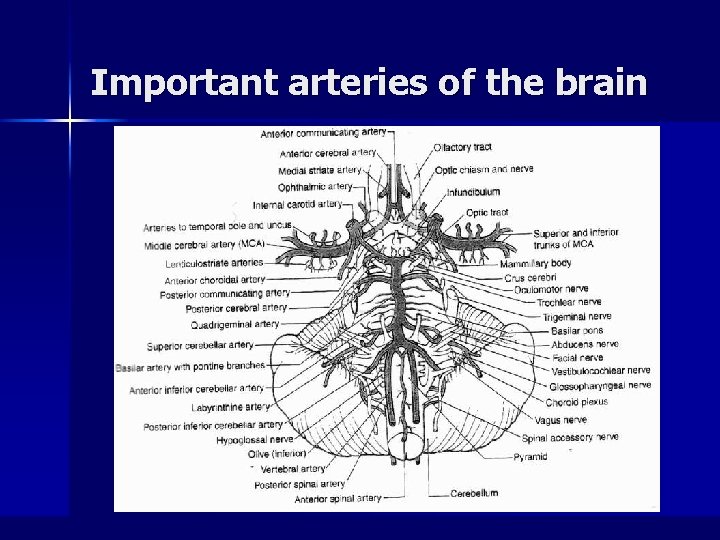

Important arteries of the brain